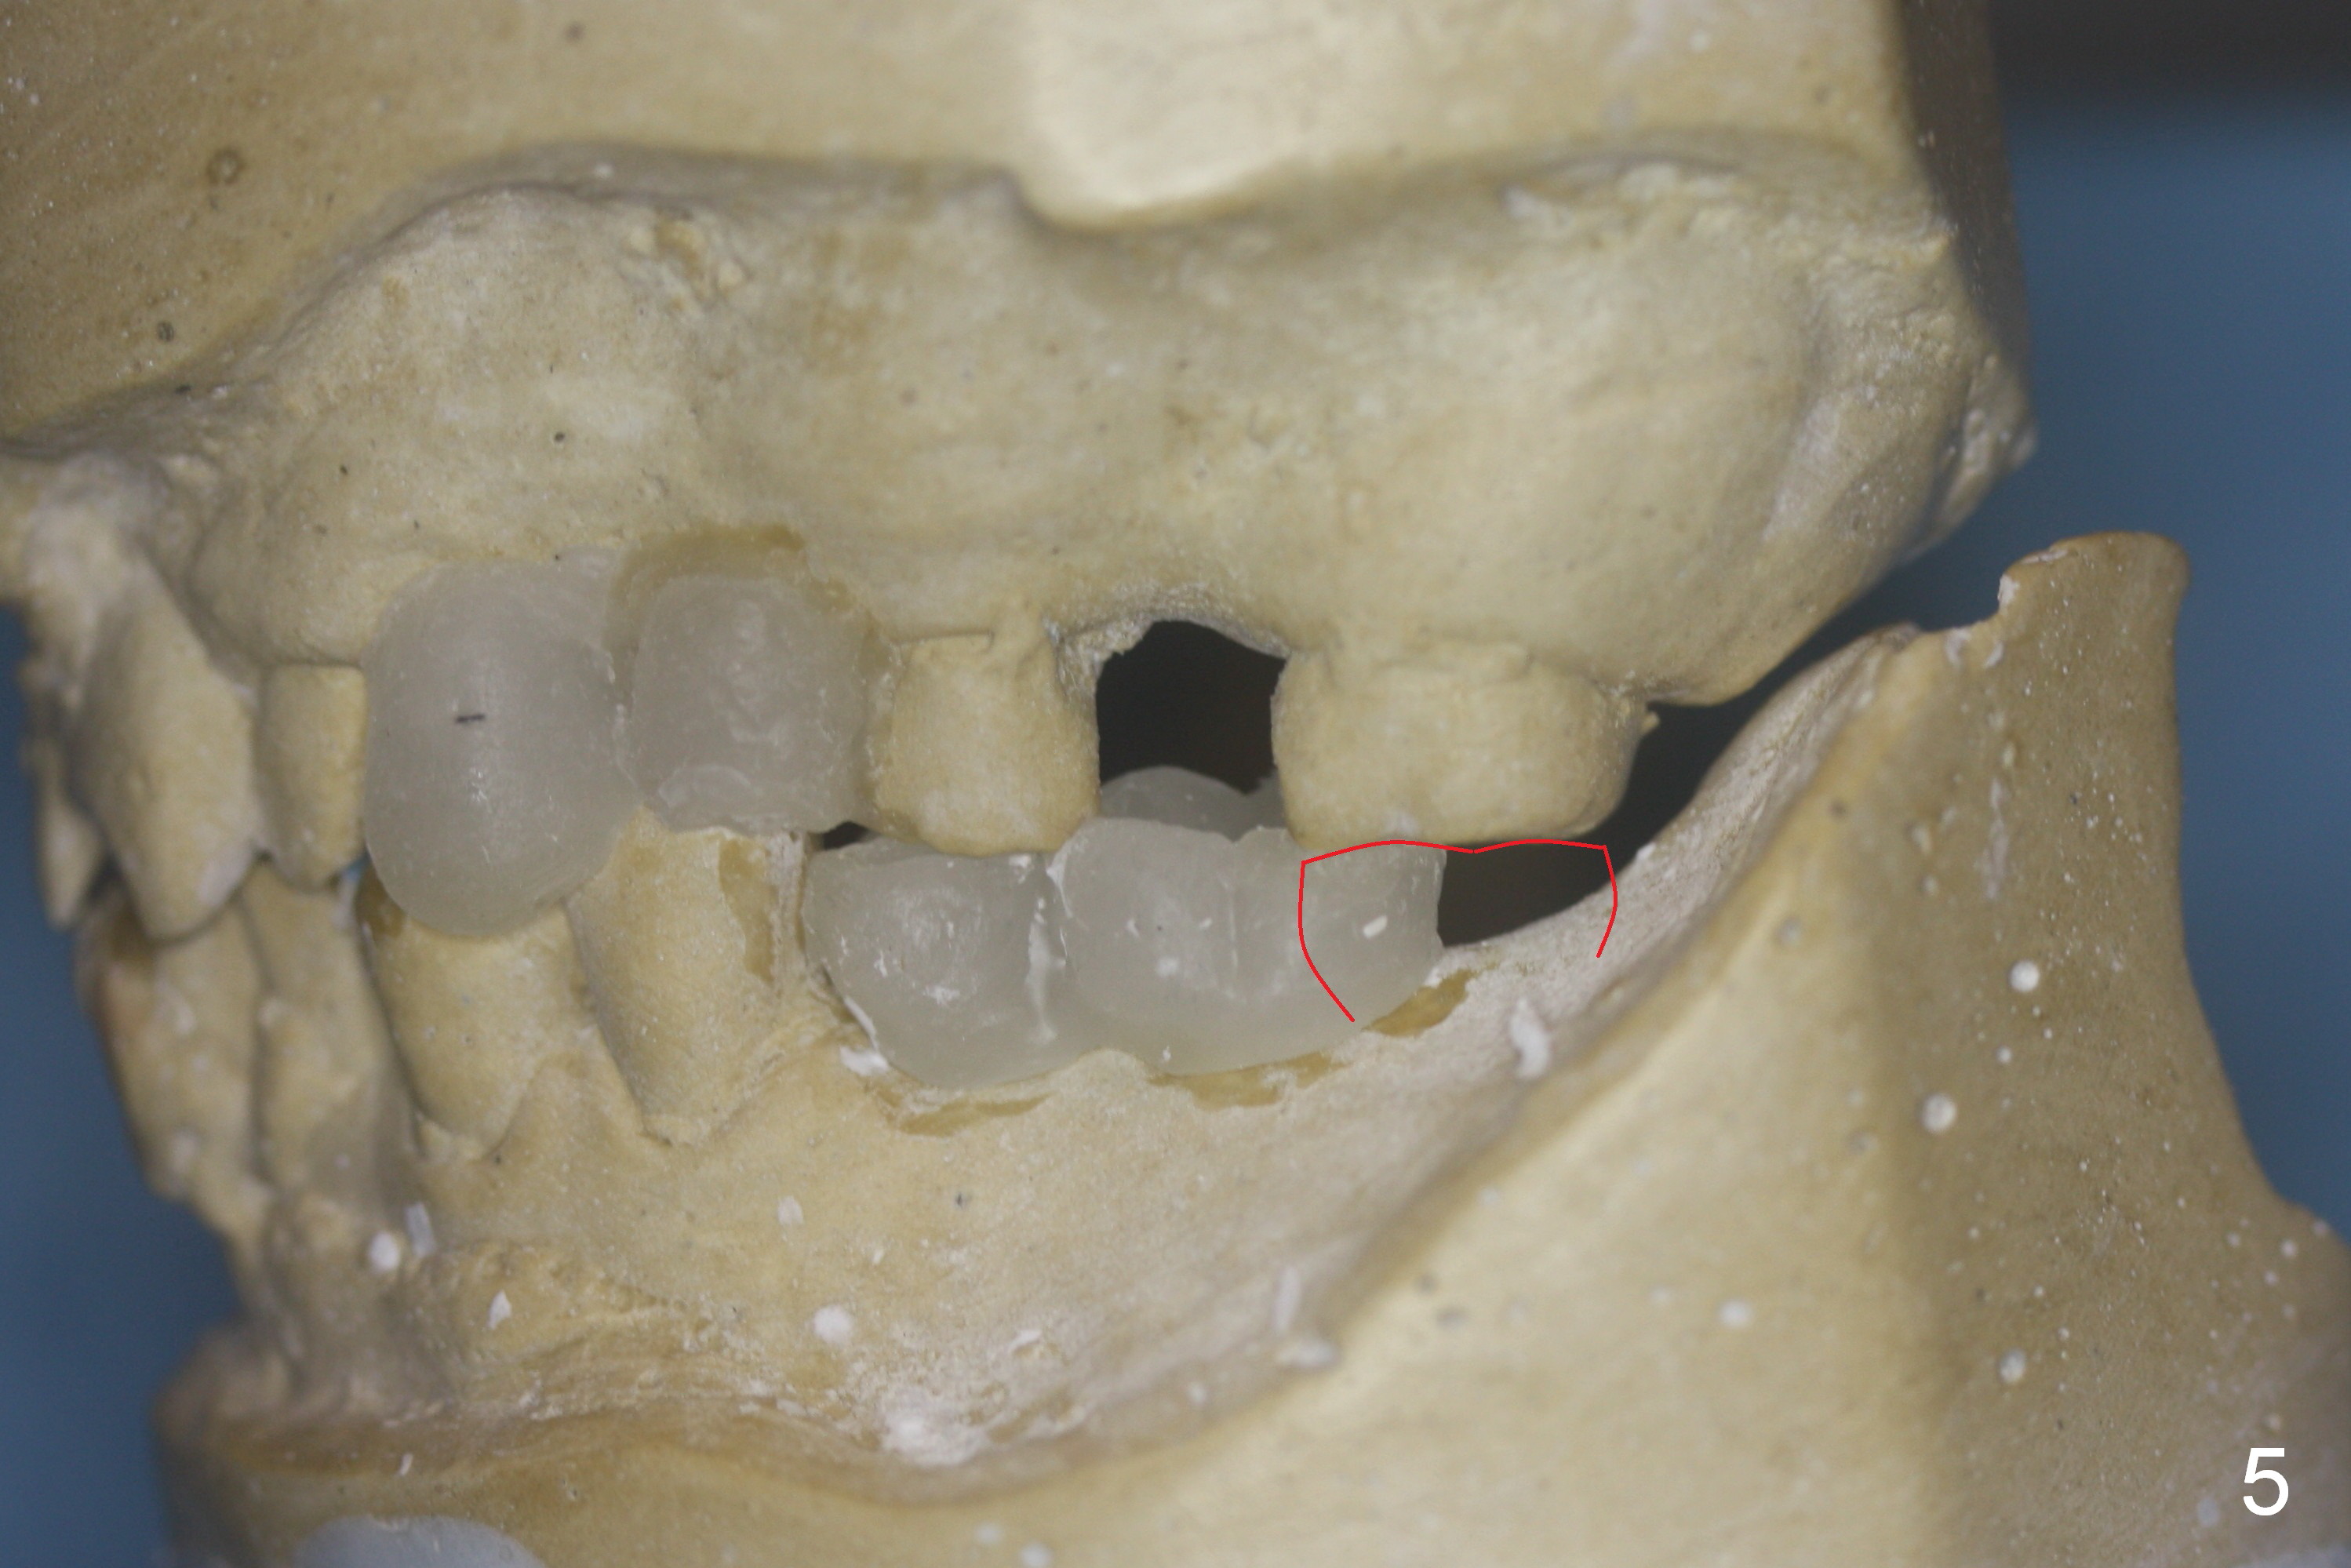

After cementation of crown at #3 and implant placement at #6, the 70-year-old lady will return for #18 and 20 implant placement and possible an immediate provisional (fixed partial denture) FPD (Fig.1,2). Before incision, start osteotomy 5 mm distal to a surgical stent (with #19 as the most distal tooth) and at #18. After incision, the initial bone depth is 11 mm (Fig.3) and insert parallel pins with depth marks for PA. If there is enough bone and bone density is low, extend the depth to 14 mm. Tatum tapered implants are going to be used. Which set of drills should be opened? Set speed at 50 RPM. Fig.3 is long horizontally. It should have been taken with #1 sensor. Beside, she is skinny. The dental arches are narrow.